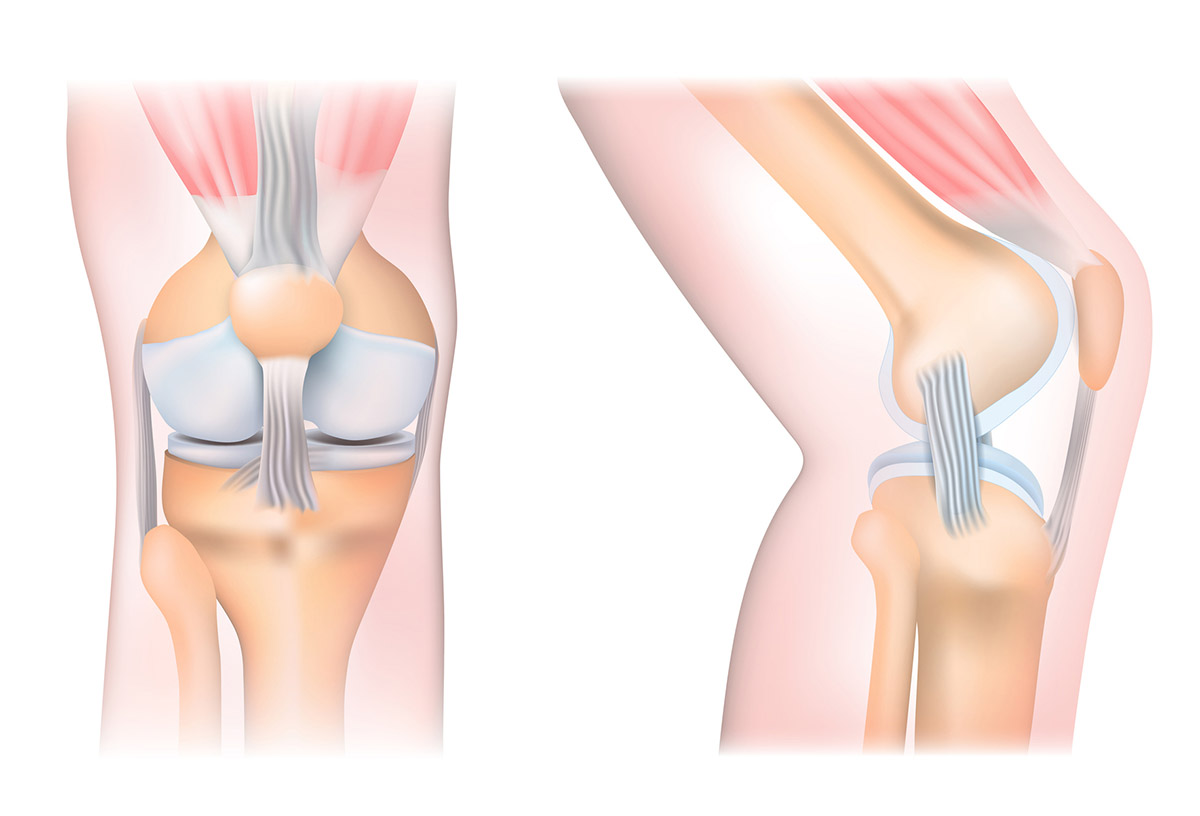

Το γόνατο είναι μια σύνθετη άρθρωση αποτελούμενη από τμήματα που έχει νόημα να γνωρίζεις, ειδικά αν έχεις ενοχλήσεις σε αυτό, προκειμένου να διακρίνεις τι ακριβώς είναι που σε ενοχλεί:

- Υποστηρίζεται από συνδέσμους που συνδέουν το οστό του άνω ποδιού (μηριαίο οστό) στο οστό του κάτω ποδιού (κνήμη). Δύο από αυτούς είναι οι πρόσθιοι και οπίσθιοι χιαστοί σύνδεσμοι, οι οποίοι διασταυρώνονται μεταξύ τους εντός της άρθρωσης και σταθεροποιούν την κίνηση.

- Στο μπροστινό μέρος της άρθρωσης «κάθεται» η επιγονατίδα για να την προστατεύει.

- Σε κάθε γόνατο υπάρχει και ο μηνίσκος, ένας χόνδρος σε σχήμα C, που μαλακώνει και προστατεύει τη σταθερότητα της άρθρωσης.

- Την άρθρωση του γόνατος περιβάλλει σαν μεμβράνη το αρθρικό υγρό. Αυτό διευκολύνει την ομαλή κίνηση, ενώ οι γύρω μύες παρέχουν δύναμη και συντονισμό για τη σωστή λειτουργία του γόνατος.

Έτσι, ένας πόνος στο γόνατο μπορεί να αφορά το μπροστινό μέρος, π.χ. την επιγονατίδα, πιο σπάνια το πίσω μέρος, τα πλαϊνά (είτε εσωτερικά είτε εξωτερικά), ή μπορεί να νιώθεις διάχυτο πόνο σε όλη την περιοχή του γόνατος.